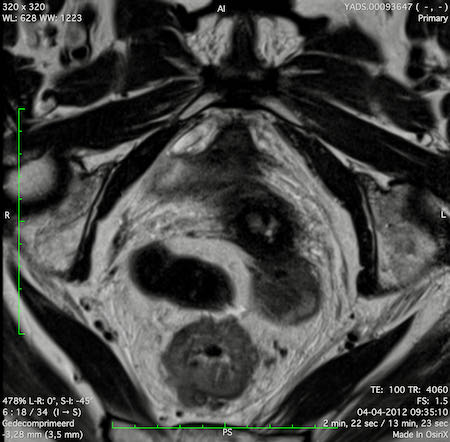

Hình ảnh

Các hình ảnh được cung cấp cho thấy ung thư biểu mô tế bào nhẫn với tình trạng dày lan tỏa thành trực tràng, hình ảnh bia bắn điển hình, và sự xâm lấn mỡ mạc treo trực tràng.